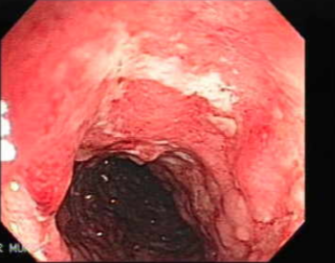

60yo male with long-standing GORD and progressive dysphagia. Most likely pathology seen on endoscopy?

Barrett’s oesophagus